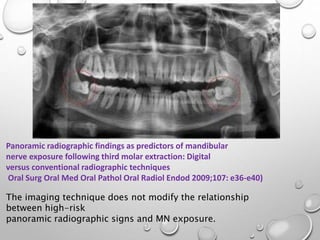

Panoramic radiographic findings as predictors of mandibular

nerve exposure following third molar extraction: Digital

versus conventional radiographic techniques

Oral Surg Oral Med Oral Pathol Oral Radiol Endod 2009;107: e36-e40)

The imaging technique does not modify the relationship

between high-risk

panoramic radiographic signs and MN exposure.